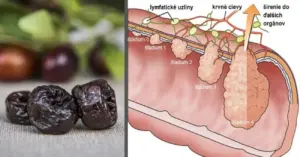

2. Blutgerinnsel

Blutgerinnsel, besonders in den Beinen, können durch Venenschwäche verursacht werden, einen Zustand, bei dem die Blutgefäße das Blut nicht effektiv zum Herzen zurücktransportieren können. Dieses Problem ist bei älteren Menschen, schwangeren Frauen und Personen, die lange sitzen oder stehen, häufig.